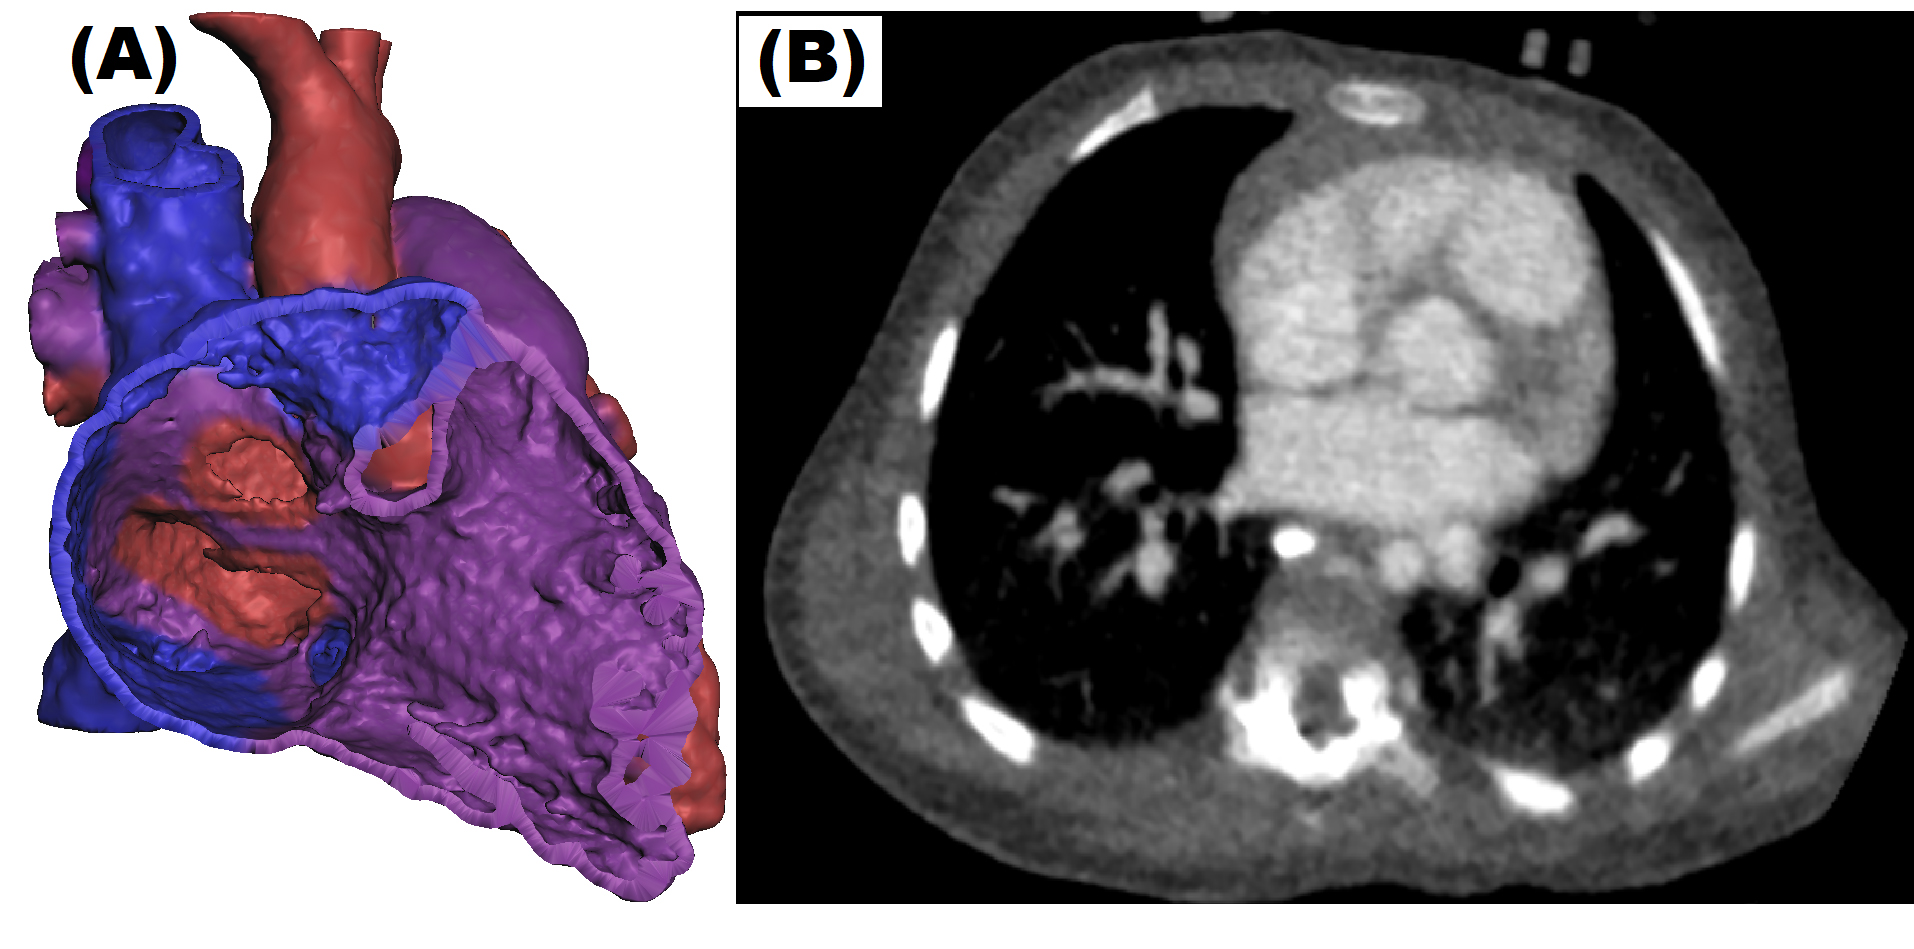

The education sessions were designed to mainly focus on anatomy and pathophysiology of ASD, VSD, ToF, and DORV. For this purpose, 3DPHM, digital 3D heart models, 2D diagrams, and digital imaging and communications in medicine (DICOM) images were utilized as the teaching tools (Figs. 2,3). The education sessions were carried out in PowerPoint lecture format, incorporating the aforementioned teaching tools with each type of CHD presented. The session was designed to mainly provide the students with a basic understanding of the morphology and hemodynamics of each type of CHD and their imaging appearances on CCTA. Each education session ran for 1.5 hour by the same investigator (I.L.) to avoid variations in teaching style between different tutors. In order to ensure the consistency between each education session, both the study and control groups received the identical learning content, apart from the 3DPHM that were only used in the education sessions for study group.

Fig. 3.

Fig. 3.Different teaching tools were used during the CHD education session. (A) Coloured digital 3D model on Meshmixer (Autodesk, San Rafael, CA, USA) in which students were able to rotate and zoom. (B) DICOM image.

The education sessions took place in a computer laboratory. At the start of the session, the students were asked to download the digital teaching materials (i.e., DICOM dataset and digital 3D heart models), so that all of the participants would be able to access them on their own computer while listening to the tutor’s explanation. After giving the students a quick revision of normal heart anatomy and general overview of acyanotic and cyanotic CHD, the session was followed by explanation of each type of chosen CHD in the following format and progression: (i) explanation of hemodynamic change using a 2D diagrams, (ii) subtypes of each CHD, (iii) possible complications if the CHD is left untreated, (iv) case study using DICOM images, digital 3D heart models, and 3DPHM. While the tutor was demonstrating the digital 3D heart models and the DICOM images on the projected screen, the participants were also encouraged to view and manipulate the digital 3D heart models and the DICOM images on their own computer using open-source software, Meshmixer (Autodesk, San Rafael, CA, USA) and RadiAnt (Medixant, Poznan, Poland). The digital 3D heart models were coloured according to the type of blood (oxygenated, deoxygenated or mixed) that the heart chamber is carrying to enable the students in achieving better understanding of the hemodynamic changes due to the CHD (Fig. 3). Using Meshmixer, the participants were allowed to rotate and zoom in the 3D models virtually. For the education sessions in which 3DPHM were used, each set of 3DPHM was shared among 3–5 students, and they were encouraged to refer to the 3DPHM freely throughout the session. 3DPHM were used to pinpoint the location of heart defects, to explain the hemodynamic changes, to highlight the malpositioning of the great arteries (if present), and to emphasize the difference in size between the major blood vessels, especially when a stenosis is present.